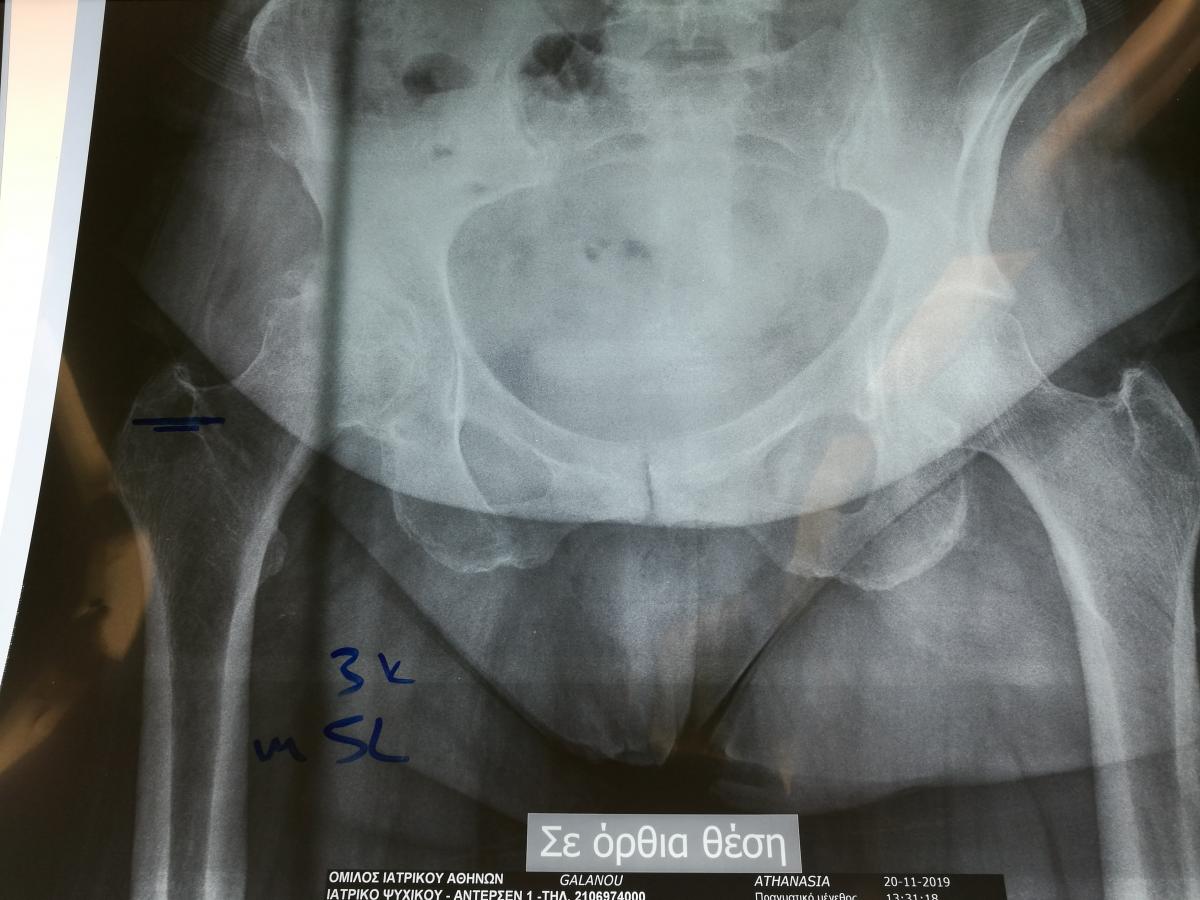

Стажування в приватній клініці у професора Христодулоса Афіни Греція листопад 2019

Компанія Lima надала стажування в ортопедичній приватній клініці місті Афіни Греція в листопаді 2019 року. Ендопротезування кульшового суглоба протезами компанії Lima малоінвазивним передньо-латеральний доступом у професора Христодулоса.